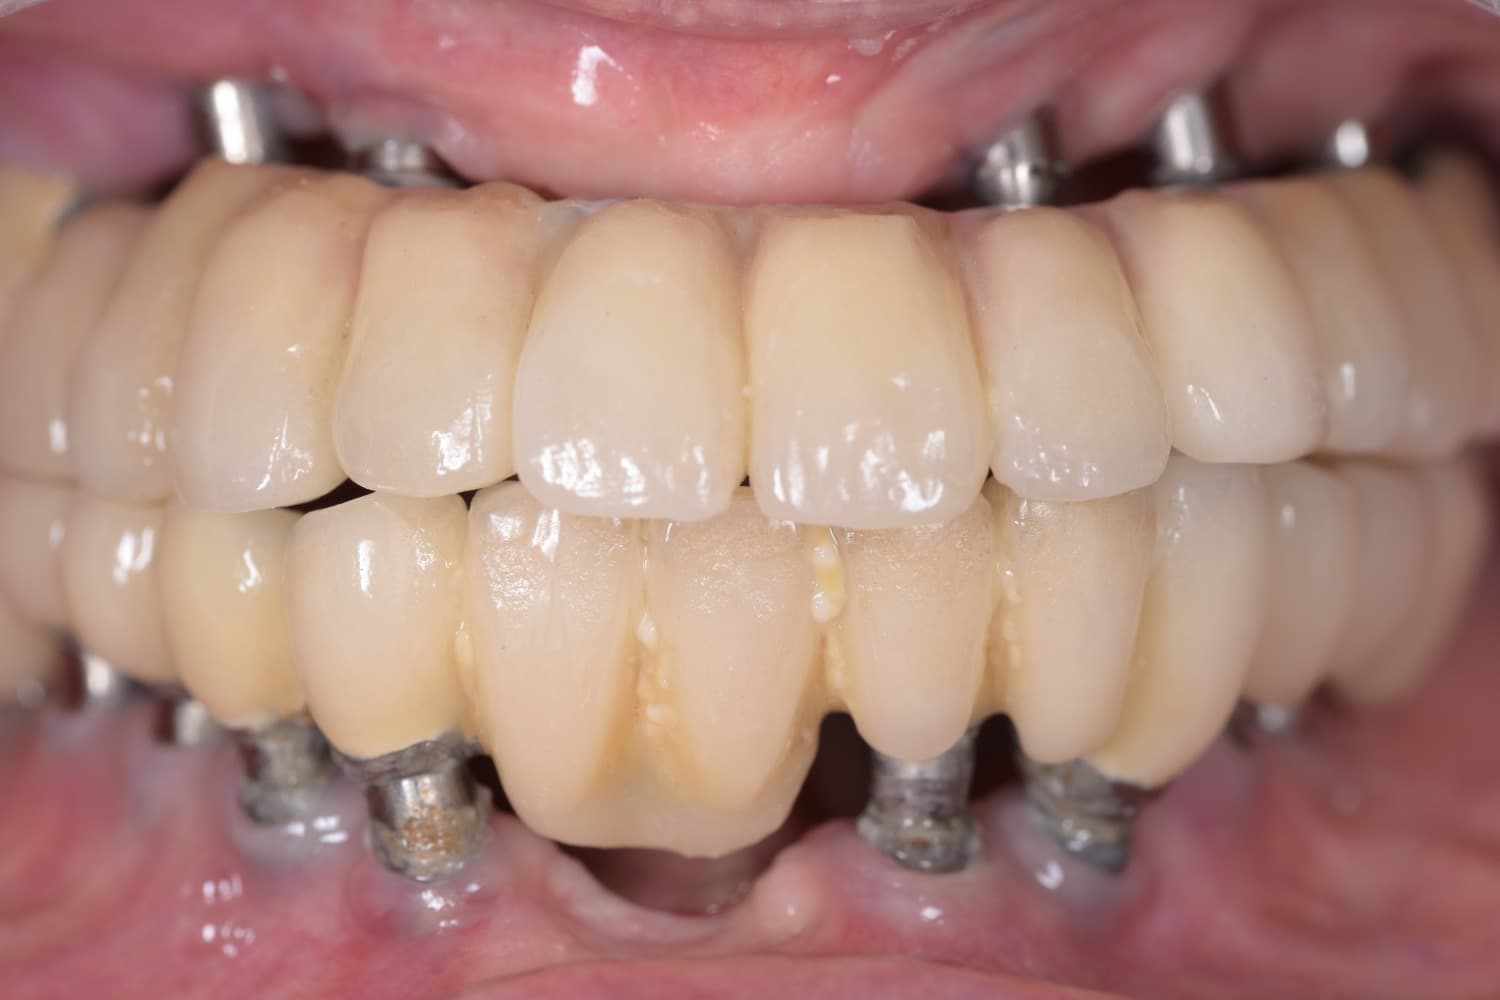

他院で埋入したインプラントの上部構造交換とインプラント周囲炎の治療(90代女性)

Before

After

他院で埋入したインプラントの上部構造交換とインプラント周囲炎の治療 90歳以上の方に外科的な処置をするのは難しいので、現状を維持するような処置で対応 その後も当院で通院して継続的なメンテナンスをおこなう 【beforeの写真について】 術前のインプラントのメインテナンスが行われていない状態 【afterの写真について】 術後のインプラント周囲炎の処置と上部構造の交換をした状態

年齢

90代

性別

女性

主訴

インプラントのメインテナンスをして欲しい

治療期間

6ヵ月

治療回数

10回

費用

300万円

副作用・リスク

継続したメインテナンスの必要性